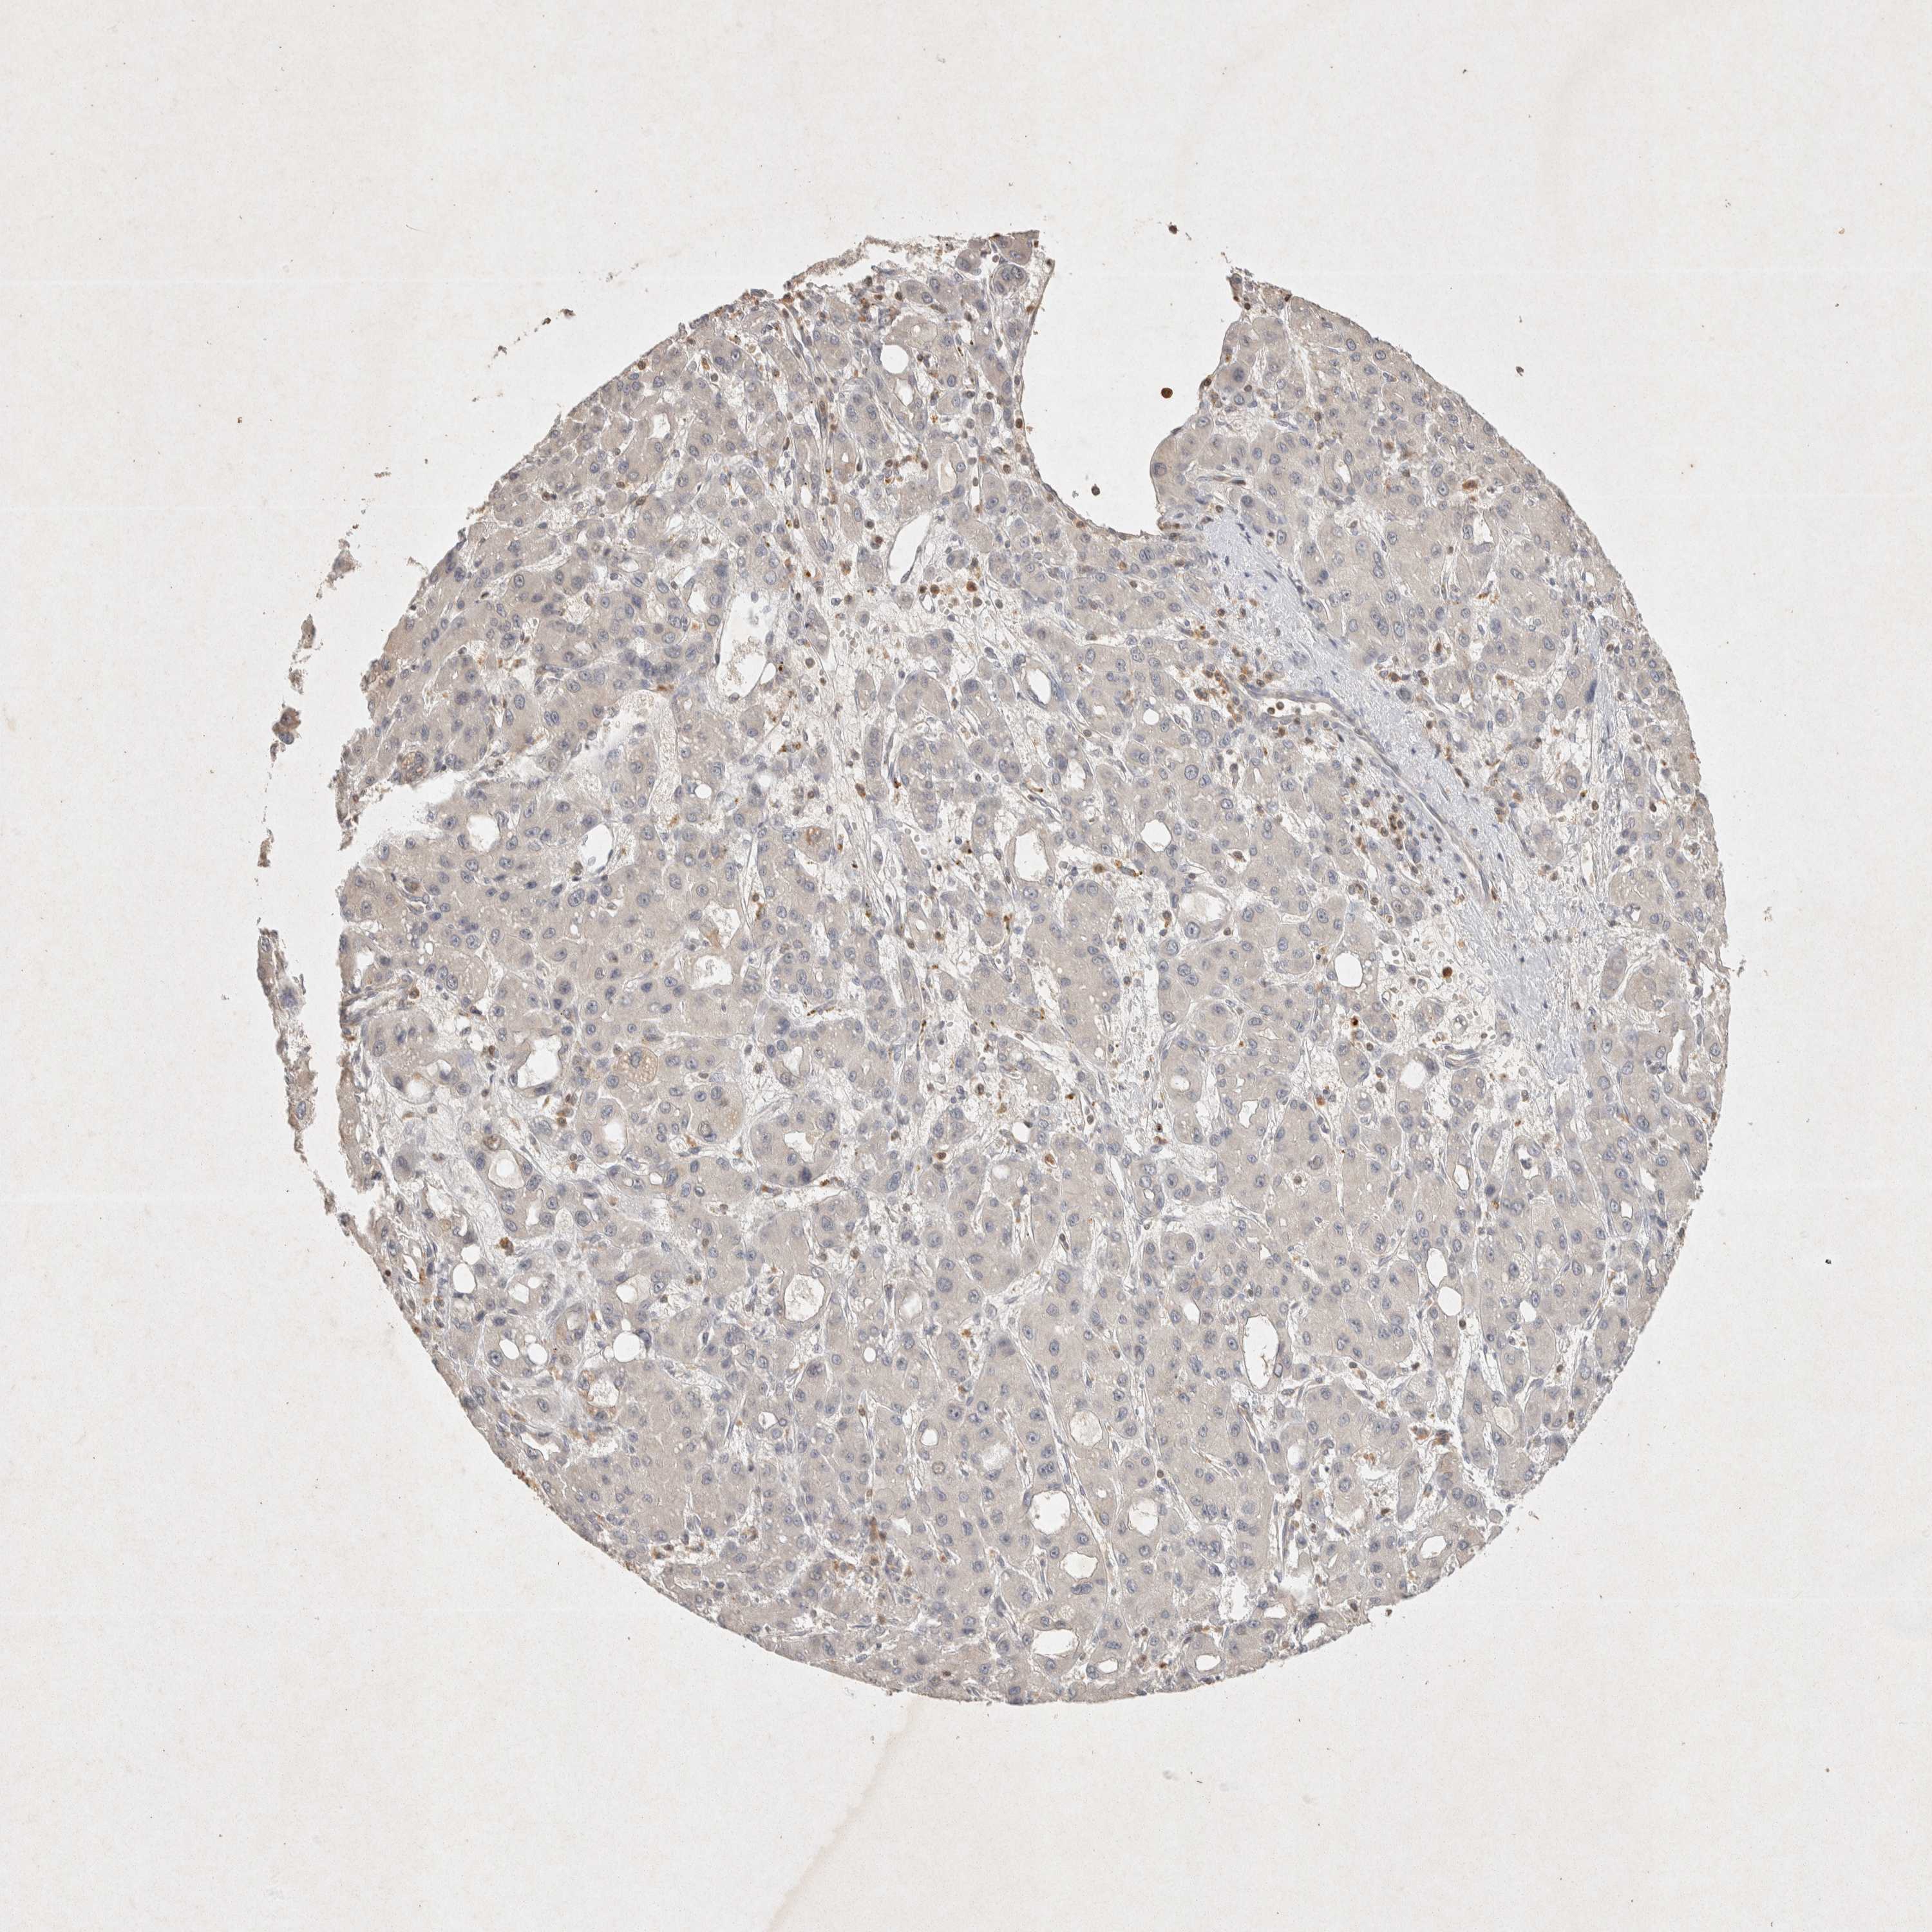

LIVER CANCER - Protein expressioni

A mouse-over function shows sample information and annotation data. Click on an image to view it in a full screen mode. Samples can be filtered based on level of antibody staining by selecting one or several of the following categories: high, medium, low and not detected. The assay and annotation is described here.

Note that samples used for immunohistochemistry by the Human Protein Atlas do not correspond to samples in the TCGA dataset.

Antibody stainingi

Antibody staining in the annotated cell types in the current human tissue is reported as not detected, low, medium, or high, based on conventional immunohistochemistry profiling in selected tissues. This score is based on the combination of the staining intensity and fraction of stained cells.

Each image is clickable and will lead to virtual microscopy that enables deeper exploration of all samples and also displays staining intensity scores, fraction scores and subcellular localization as well as patient and tissue information for each sample.

Antibody HPA047820

Antibody CAB022946

Staining

High

Medium

Low

Not detected

Intensity

Strong

Moderate

Weak

Negative

Quantity

>75%

75%-25%

<25%

None

Location

Nuclear

Cytoplasmic/membranous

Cytoplasmic/membranous,nuclear

Cholangiocarcinoma

Carcinoma, Hepatocellular, NOS